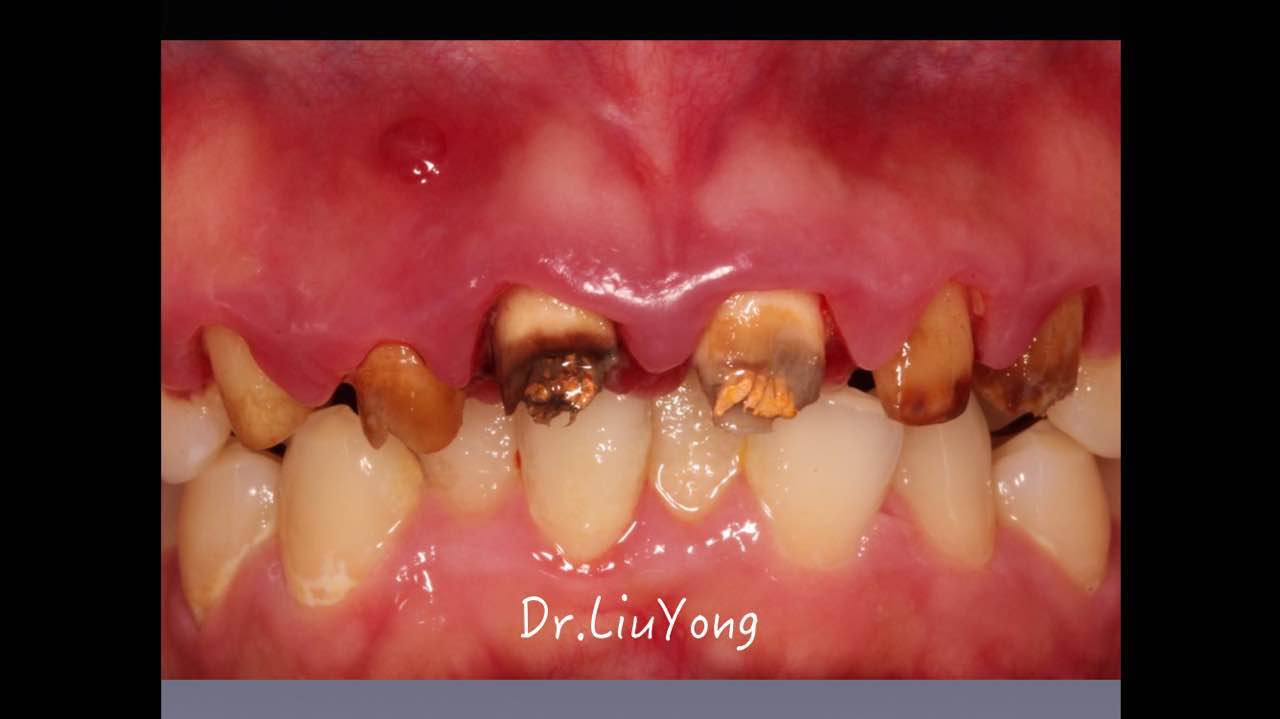

嚴重破壞生物學寬度,根尖瘺管,重行根管治療, 第一次冠延長建立唇腭側(cè)及鄰面BW,術后牙齦扇貝形差, 齦乳頭黑三角,再次行美學冠延長,建立牙齦扇貝形,手術免費, 患者因經(jīng)濟原因只能選擇鑄樁及鈷鉻合金烤瓷冠。終于完工